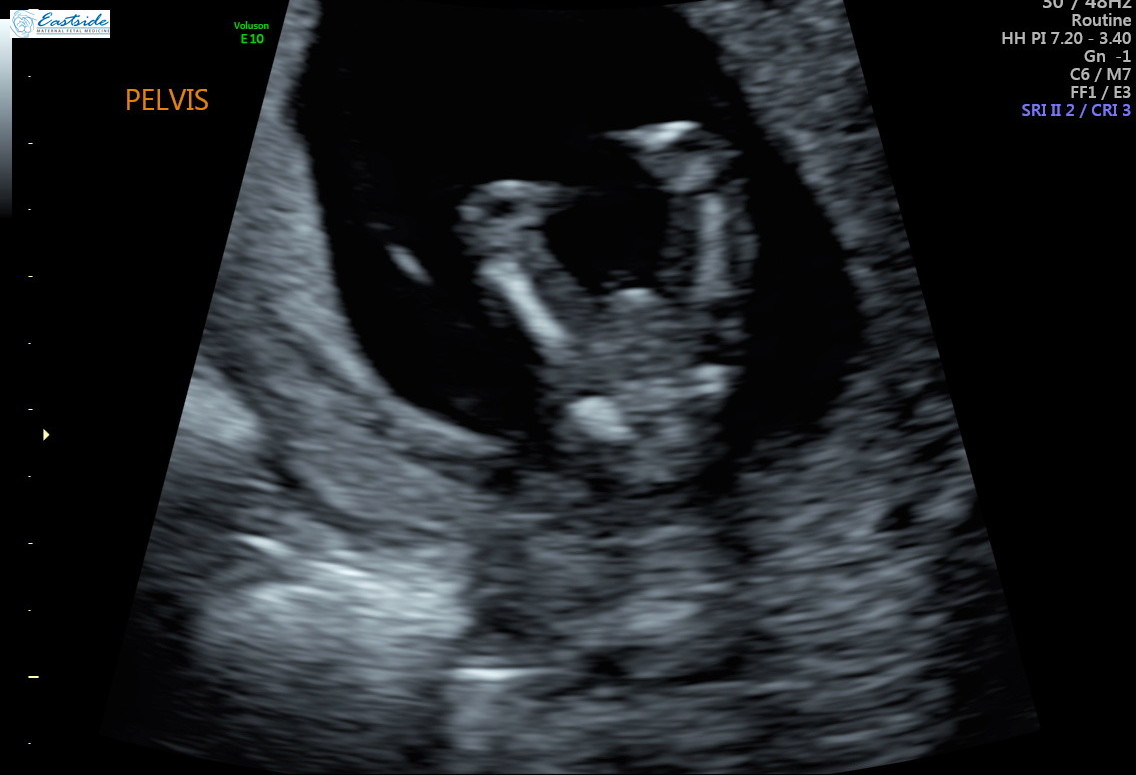

I am wondering if any experts or experienced could review the pics from my 13 week ultrasound? The tech said she was 80% sure of gender, but is it obvious to any of you? We have 3 girls so as you might guess, we are a bit anxious to find out!

Thanks! Attachment 38878Attachment 38879Attachment 38880Attachment 38881Attachment 38882Attachment 38883